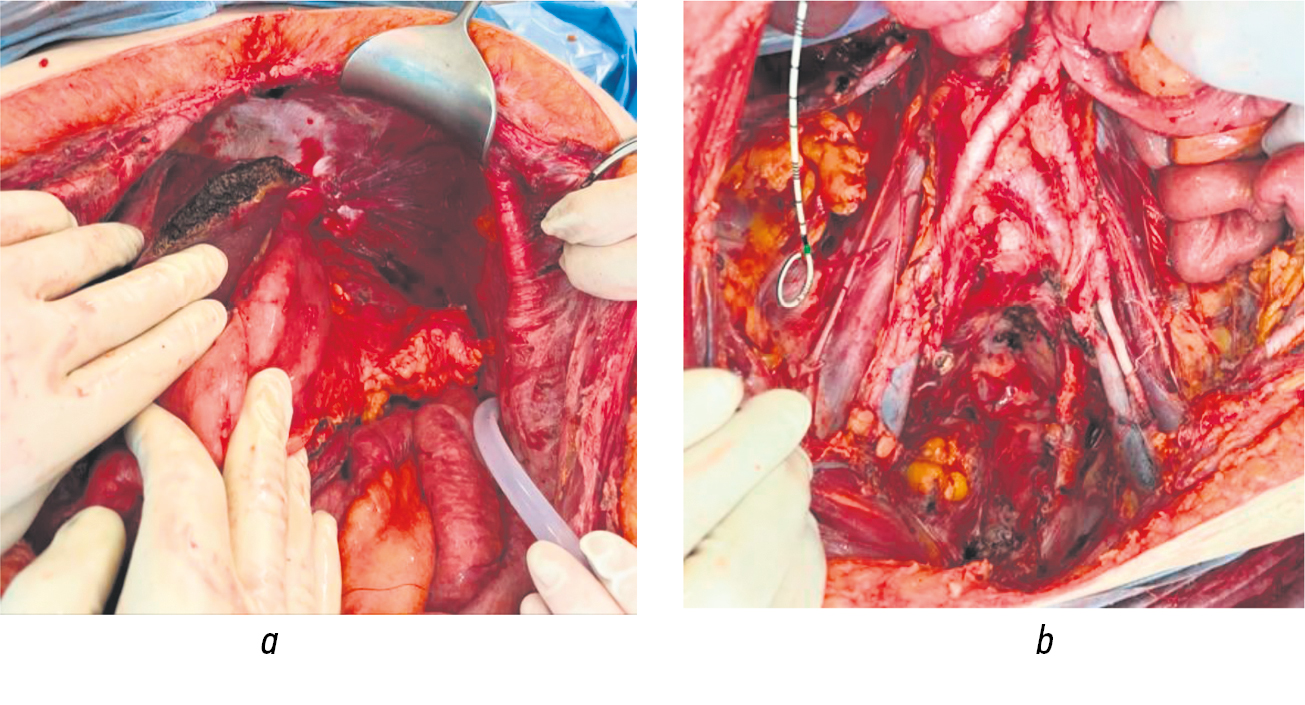

В этой связи если в случаях нарушений кишечной проходимости существует определенная вероятность устранения развившегося осложнения консервативными методами либо симптоматическими вмешательствами, то некроз первичных опухолей и метастатических очагов по сути является абсолютным (безальтернативным) показанием к применению активной хирургической тактики, одним из вариантов который является применение циторедуктивной технологии (рис. 1).

Рис. 1. Рак яичников, осложненный субкомпенсированным нарушением проходимости тонкой и толстой кишок (а). Некроз местнораспространенной опухоли прямой кишки канцероматоза брюшины (b)